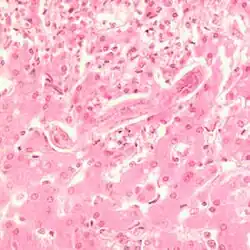

The worms can occasionally cause an aortic aneurysm during their migration, but often infested dogs are asymptomatic. In the esophagus itself, S. lupi causes a granulomatous tissue reaction, which without treatment very often degenerates and then forms various malignant tumors. In addition to squamous cell carcinomas and fibrosarcomas, the esophageal cells can also degenerate into osteosarcomas.[28] The tumor-induced space-occupying lesion in the thorax can also lead to hypertrophic osteopathy.

In the intestine, the muscle meat and cyst capsules are digested, releasing the larvae, which penetrate the mucosa of the duodenum and jejunum. There they develop into adult trichinae within about four days. After mating, the female worms bore deeper into the mucosa and lay up to 1500 eggs per individual over four to 16 weeks. The hatched larvae are about 100 microns long. They migrate first into the lymphatic vessels and then via the portal vein into the peripheral vascular system. Once they reach the musculature in the process, they leave the blood vessel and bore into a single muscle fiber. There they grow rapidly to a length of 1 mm, encapsulate and begin to take on the typical curled shape. Capsule formation in muscle tissue begins about 15 days after infection and is complete after four to eight weeks - the host's flesh is then infectious. Larvae can remain infectious in the muscles of a host for years; they are most commonly found in the diaphragm, tongue, masseter muscles, and intercostal muscles.[65]